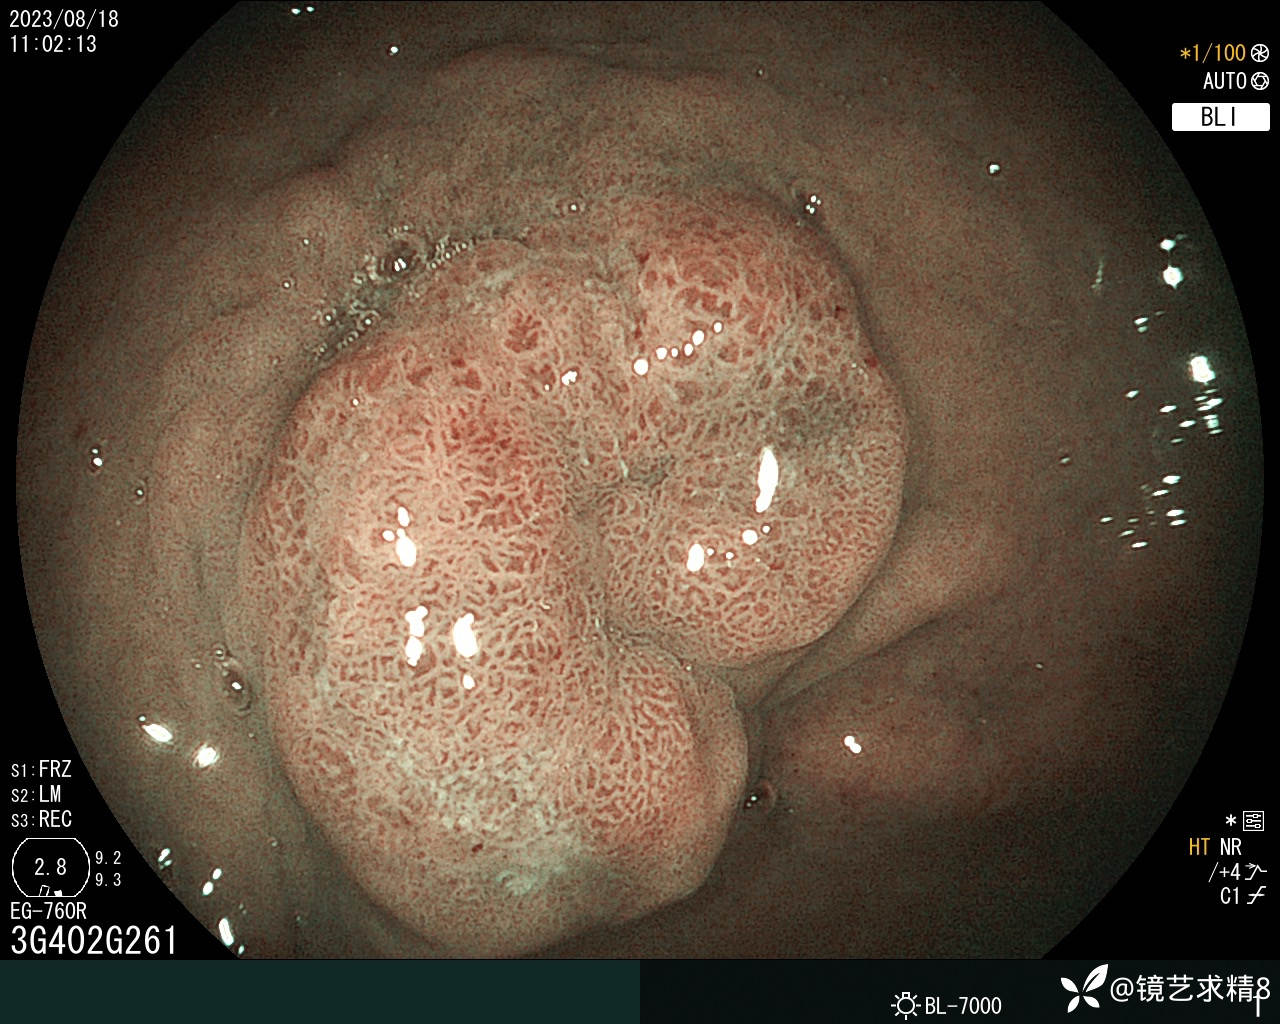

胃窦:黏膜红白相间,前壁与小弯侧交界近幽门见一0-Ia+IIc型病变,约20*30mm大小,BLI染色局部呈淡茶色,边界可见,表面结构欠规则,取病检2块+HP检查,质软。

内镜下诊断:1. 胃窦0-Ia+Ic型病变,不除外早期ca?请结合病检+HP检查